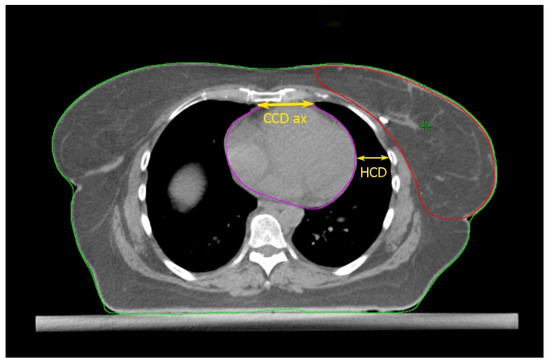

2.2. The Cardiac Contact Distance in the Axial (CCDax) and Parasagittal (CCDps) Planes and the Lateral Heart-to-Chest Distance (HCD)